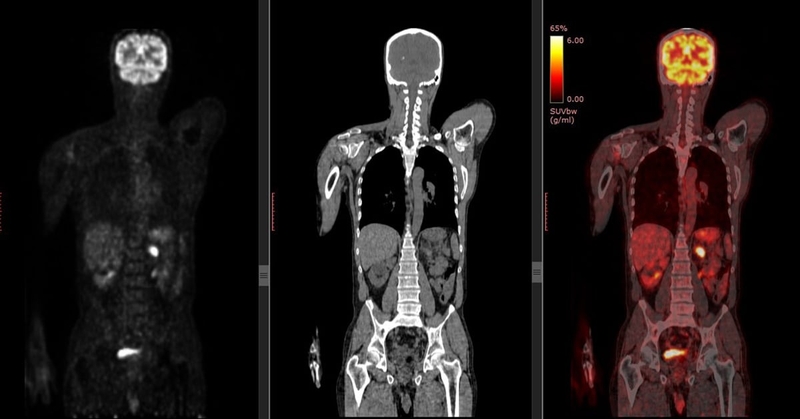

• Chụp cắt lớp phát xạ Positron (PET): Đây là một xét nghiệm cao cấp hơn sử dụng để xem liệu khối u là lành tính (không phải ung thư) hay ác tính (ung thư).

Chụp PET CT là một trong những xét nghiệm giúp chẩn đoán bệnh